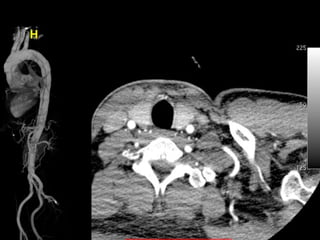

74 yo Female

Chronic Cought, HHD, ASHD

Heavy breath during last 3 mo

Family history (+)

Total

debranching